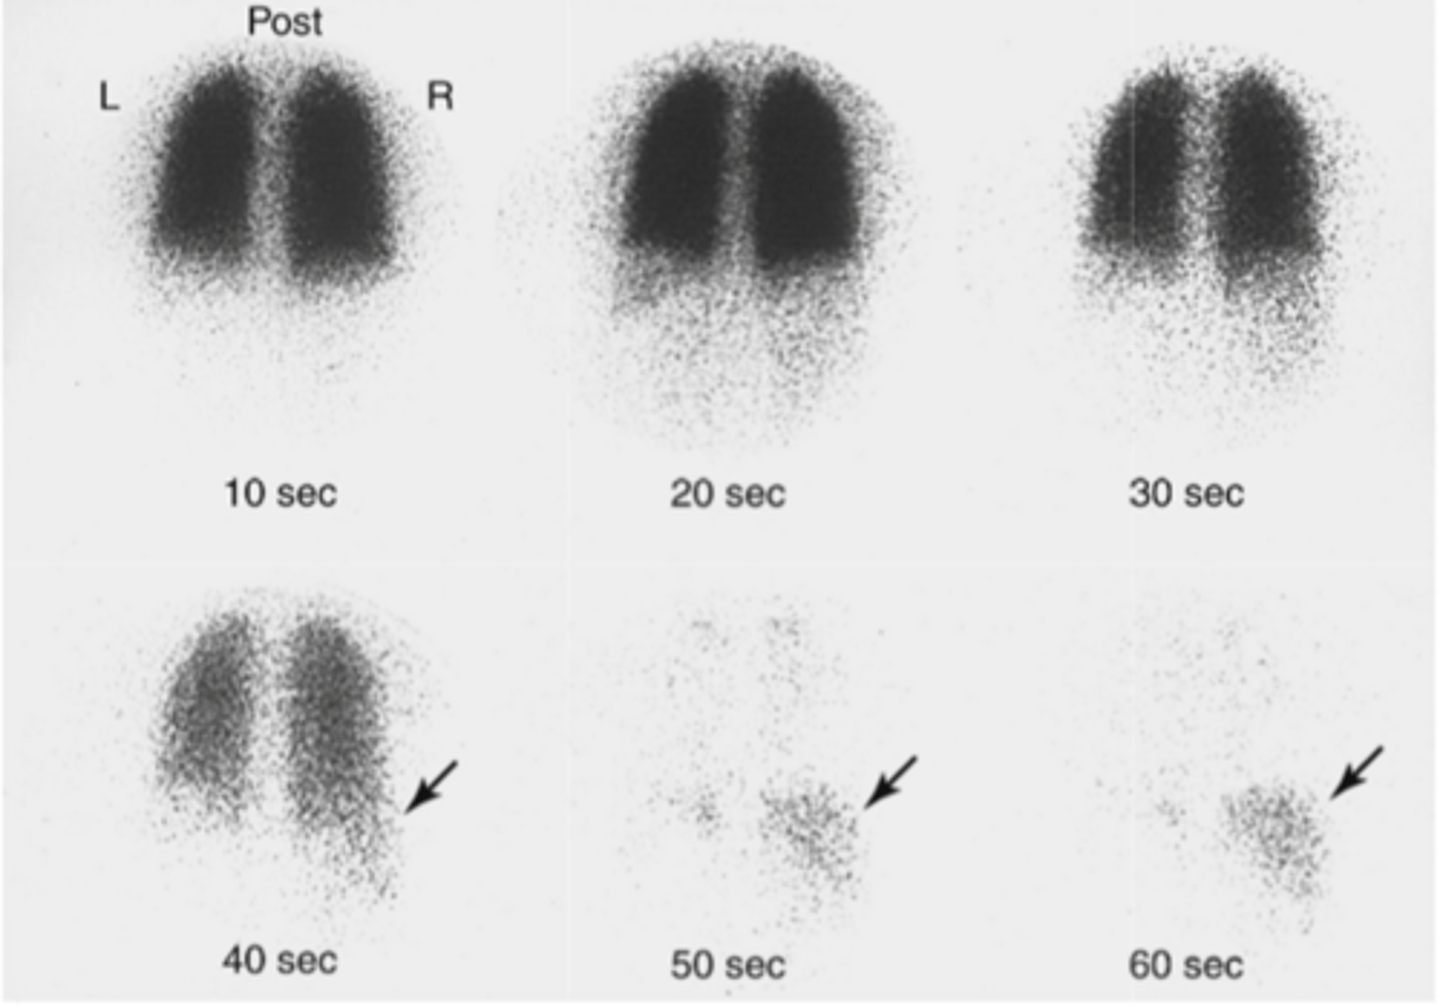

when a drug or radioactive tracer is labelled with an unstable radionucleotide, the resulting radiation can be used to follow the tracer in the body

example: the use of flourine-18 on a biologically active molecule fludeoxyglucose ( FDG) which emits positrons. its introduced into the body and the emissions can be observed all around the body with varying concentrations

FDG is a good reflection of the glucose uptake by cells in the body